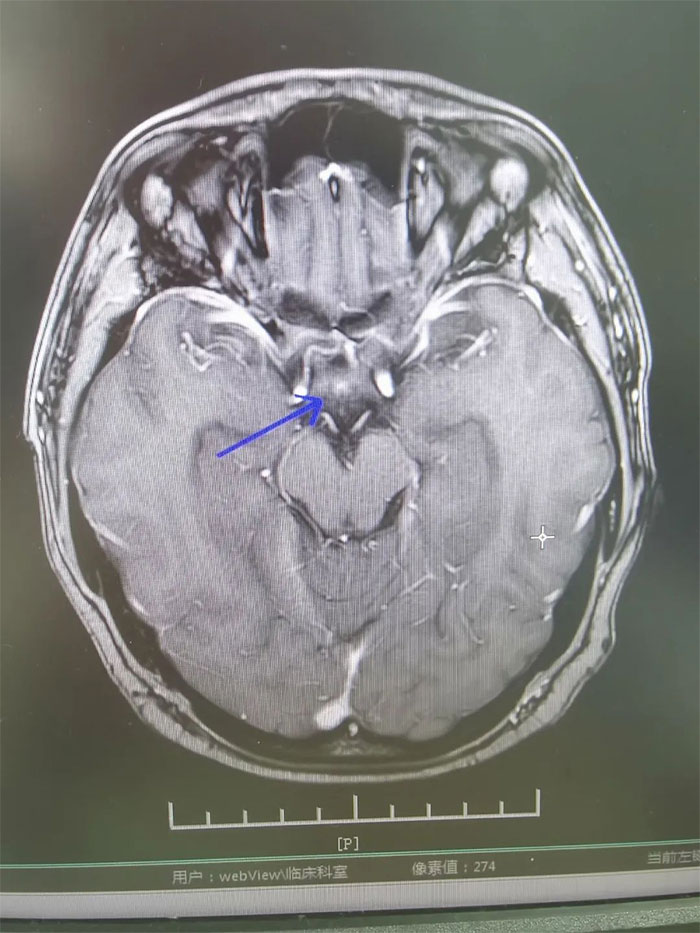

▲ 放療后復(fù)查,病灶明顯縮小

經(jīng)過一個完整療程的放療,患者沒有出現(xiàn)明顯并發(fā)癥,頭痛、惡心嘔吐癥狀得到緩解。復(fù)查MRI,影像顯示病灶明顯縮小,梗阻性腦積水消失。進一步完善檢查評估后,小剛已順利出院。眼見短時間內(nèi)病情即得到控制,小剛對生活又重拾信心,表示一定會以積極的心態(tài)面對人生。